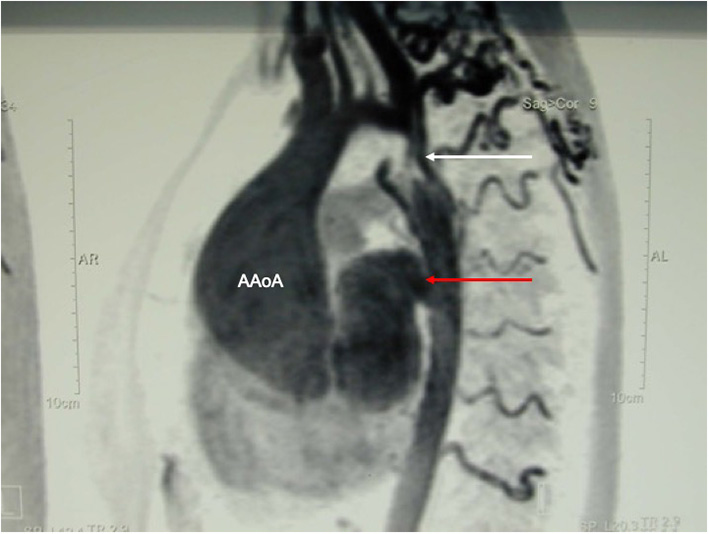

Figure 10

MR-angiography showing a large aneurysm of the ascending aorta (AaoA), a hypoplastic aortic arch and a recurrent stenosis following previous coarctation repair (white arrow) and enlarged intercostal arteries as sign of collateralization. In addition, there was a large pseudoaneurysm at the site of a Dacron patch used for initial coarctation repair (red arrow).